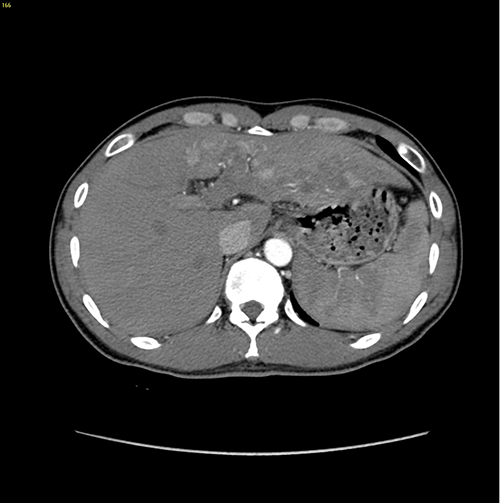

左肝癌并门静脉左支癌栓---左半肝切除